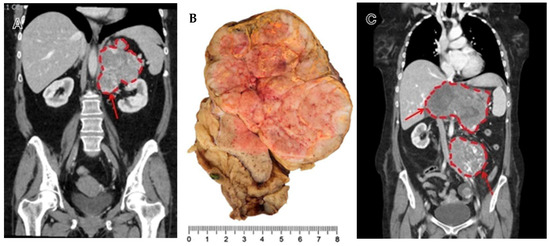

| Areas suspicious of necrosis in cross-sectional imaging 1 | Yes No | 32 (48%) 35 (52%) | 10 (25%) 30 (75%) | 22 (81%) 5 (19%) | <0.001 |

| Areas suspicious of necrosis in histology 1 | Yes No | 27 (40%) 40 (60%) | 1 (2.5%) 39 (97.5%) | 26 (96%) 1 (4%) | <0.001 |